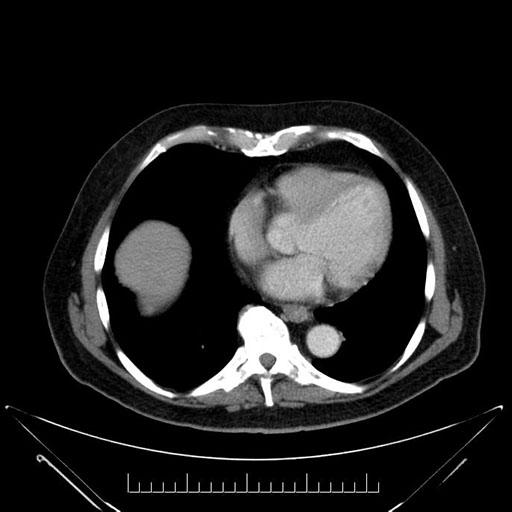

Imaging Analysis

Look through the patient's CT scan to identify any areas of concern for the necessary procedure.

Based on your CT findings, which issue(s) would give reason for "planned slowing down moment(s)" in this case?